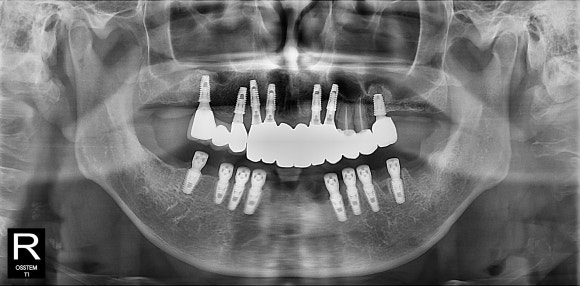

3개월 후에는

임시치아와 동일한 모양의

세멘트 없는

고퀄리티 스크류 타입 보철물

장착하고 마무리 하게 됩니다 ^^